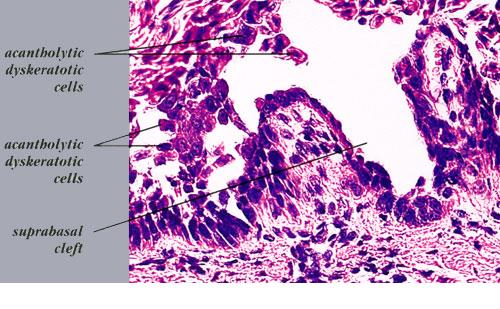

The characteristic changes in Darier’s disease include the following: (a) a peculiar form of dyskeratosis resulting in the formation of corps ronds and grains; (b) suprabasal acantholysis leading to the formation of suprabasal clefts or lacunae; and (c) irregular upward proliferation into the lacunae of papillae lined with a single layer of basal cells, so-called villi (Fig. 6-27). There are also papillomatosis, acanthosis, and hyperkeratosis. The dermis shows a chronic inflammatory infiltrate. In some cases, there is downward proliferation of epidermal cells into the dermis.

The corps ronds occur in the upper stratum malpighii, particularly in the granular and horny layers; grains are found in the horny layer and as acantholytic cells within the lacunae. Corps ronds possess a central homogeneous, basophilic,

pyknotic nucleus that is surrounded by a clear halo. By virtue of size and the conspicuous halo, corps ronds stand out clearly . Peripheral to the halo lies basophilic dyskeratotic material as a shell . The nonstaining halo in some instances is partially replaced by homogeneous, eosinophilic dyskeratotic material . Compared with the corps ronds, the grains are much less conspicuous. They resemble parakeratotic cells but are somewhat larger. The nuclei of grains are elongated and often grain shaped and are surrounded by homogeneous dyskeratotic material that usually stains basophilic but may stain eosinophilic. The lacunae represent small, slitlike intraepidermal vesicles most commonly located directly above the basal layer. They contain acantholytic cells and show premature partial keratinization. Because of shrinkage, some of them are elongated, and these then appear identical with the grains in the horny layer. The villi projecting into the lacunae may be quite tortuous, so on histologic examination, some of them appear in cross section as rounded dermal structures lined by a solitary row of basal cells .